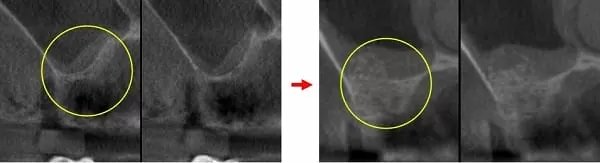

治療前:第一小臼齒發炎導致外側骨破洞 → 治療後:拔除後窩洞填入骨粉及膠原蛋白

治療前:鼻竇非常低 → 治療後:墊高鼻竇,填入大量骨粉

手術後一周傷口癒合情況 → 手術後二周傷口完全癒合